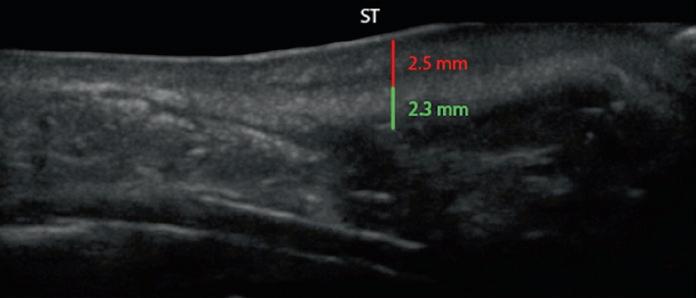

Fig. 1.21 Patient with a thick-skin STE composed of a thick lower part and thin upper part. (a, b) Preop sonogram and photo. (c , d) Views 4 weeks postop, prior to start of Accutane®. (e, f ) Views 4 months after surgery and 3 month course of Accutane. The vertical measurements show dermis (red ) and SMAS ( green). Note: there has been a full 1 mm thinning of the dermis (33%) and 0.6 mm of the deep soft tissue (25%). ST supratip; T tip

Patients who have a thick dermis benefit from preconditioning with a combination of salicylic acid, mechanical scrub, alpha hydroxyl acids, and retinoids to shrink the oil glands. Patients who have thick underlying soft tissue are routinely defatted using an open approach by dissecting at a subdermal level, followed by resection of the intervening soft tissues down to the cartilage level. Selected patients benefit from a postoperative treatment program with either 20 mg of isotretinoin (Accutane®) started at 4 weeks and continued for 4–5 months to decrease the size of the oil glands, with optional CO2 Fraxel® (Solta Medical; Hayward, CA) for textural smoothing. The patient shown in Fig. 1.21 had extremely thick skin, which was defatted intraoperatively. A dorsal graft was inserted to unify the two skin sleeves. sonogram